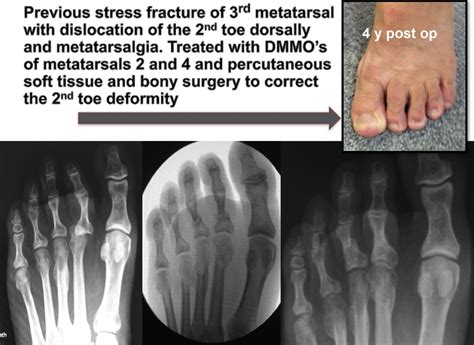

Best treatment for Metatarsalgia? - Footcare Scotland